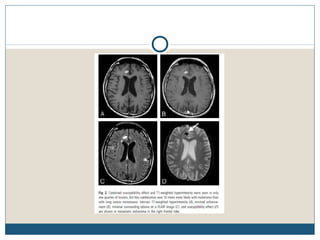

CÉREBRO

 A freqüência de metástases cerebrais é maior com melanoma do

que para a maioria das outras doenças malignas.

 Metástases no SNC são a segunda causa mais comum de

mortalidade.

 Na TC, metástases intracranianas podem aumentar uniformemente

ou em um padrão em forma de anel. Padrões similares são vistos em

RM.

 RM do cérebro é o procedimento de escolha para os sintomas

atribuíveis ao SNC, e é opcional para os pacientes assintomáticos

com estágio III ou IV da doença.

 A indicação para os exames de rotina do cérebro em pacientes

assintomáticos com doença loco-regional avançada é controversa.

Alguns especialistas defendem estudos para procurar envolvimento

do SNC apenas em pacientes sintomáticos.

CÉREBRO  A freqüênciade metástases cerebrais é maior com melanoma do que para a maioria das outras doenças malignas.  Metástases no SNC são a segunda causa mais comum de mortalidade.  Na TC, metástases intracranianas podem aumentar uniformemente ou em um padrão em forma de anel. Padrões similares são vistos em RM.  RM do cérebro é o procedimento de escolha para os sintomas atribuíveis ao SNC, e é opcional para os pacientes assintomáticos com estágio III ou IV da doença.  A indicação para os exames de rotina do cérebro em pacientes assintomáticos com doença loco-regional avançada é controversa. Alguns especialistas defendem estudos para procurar envolvimento do SNC apenas em pacientes sintomáticos.